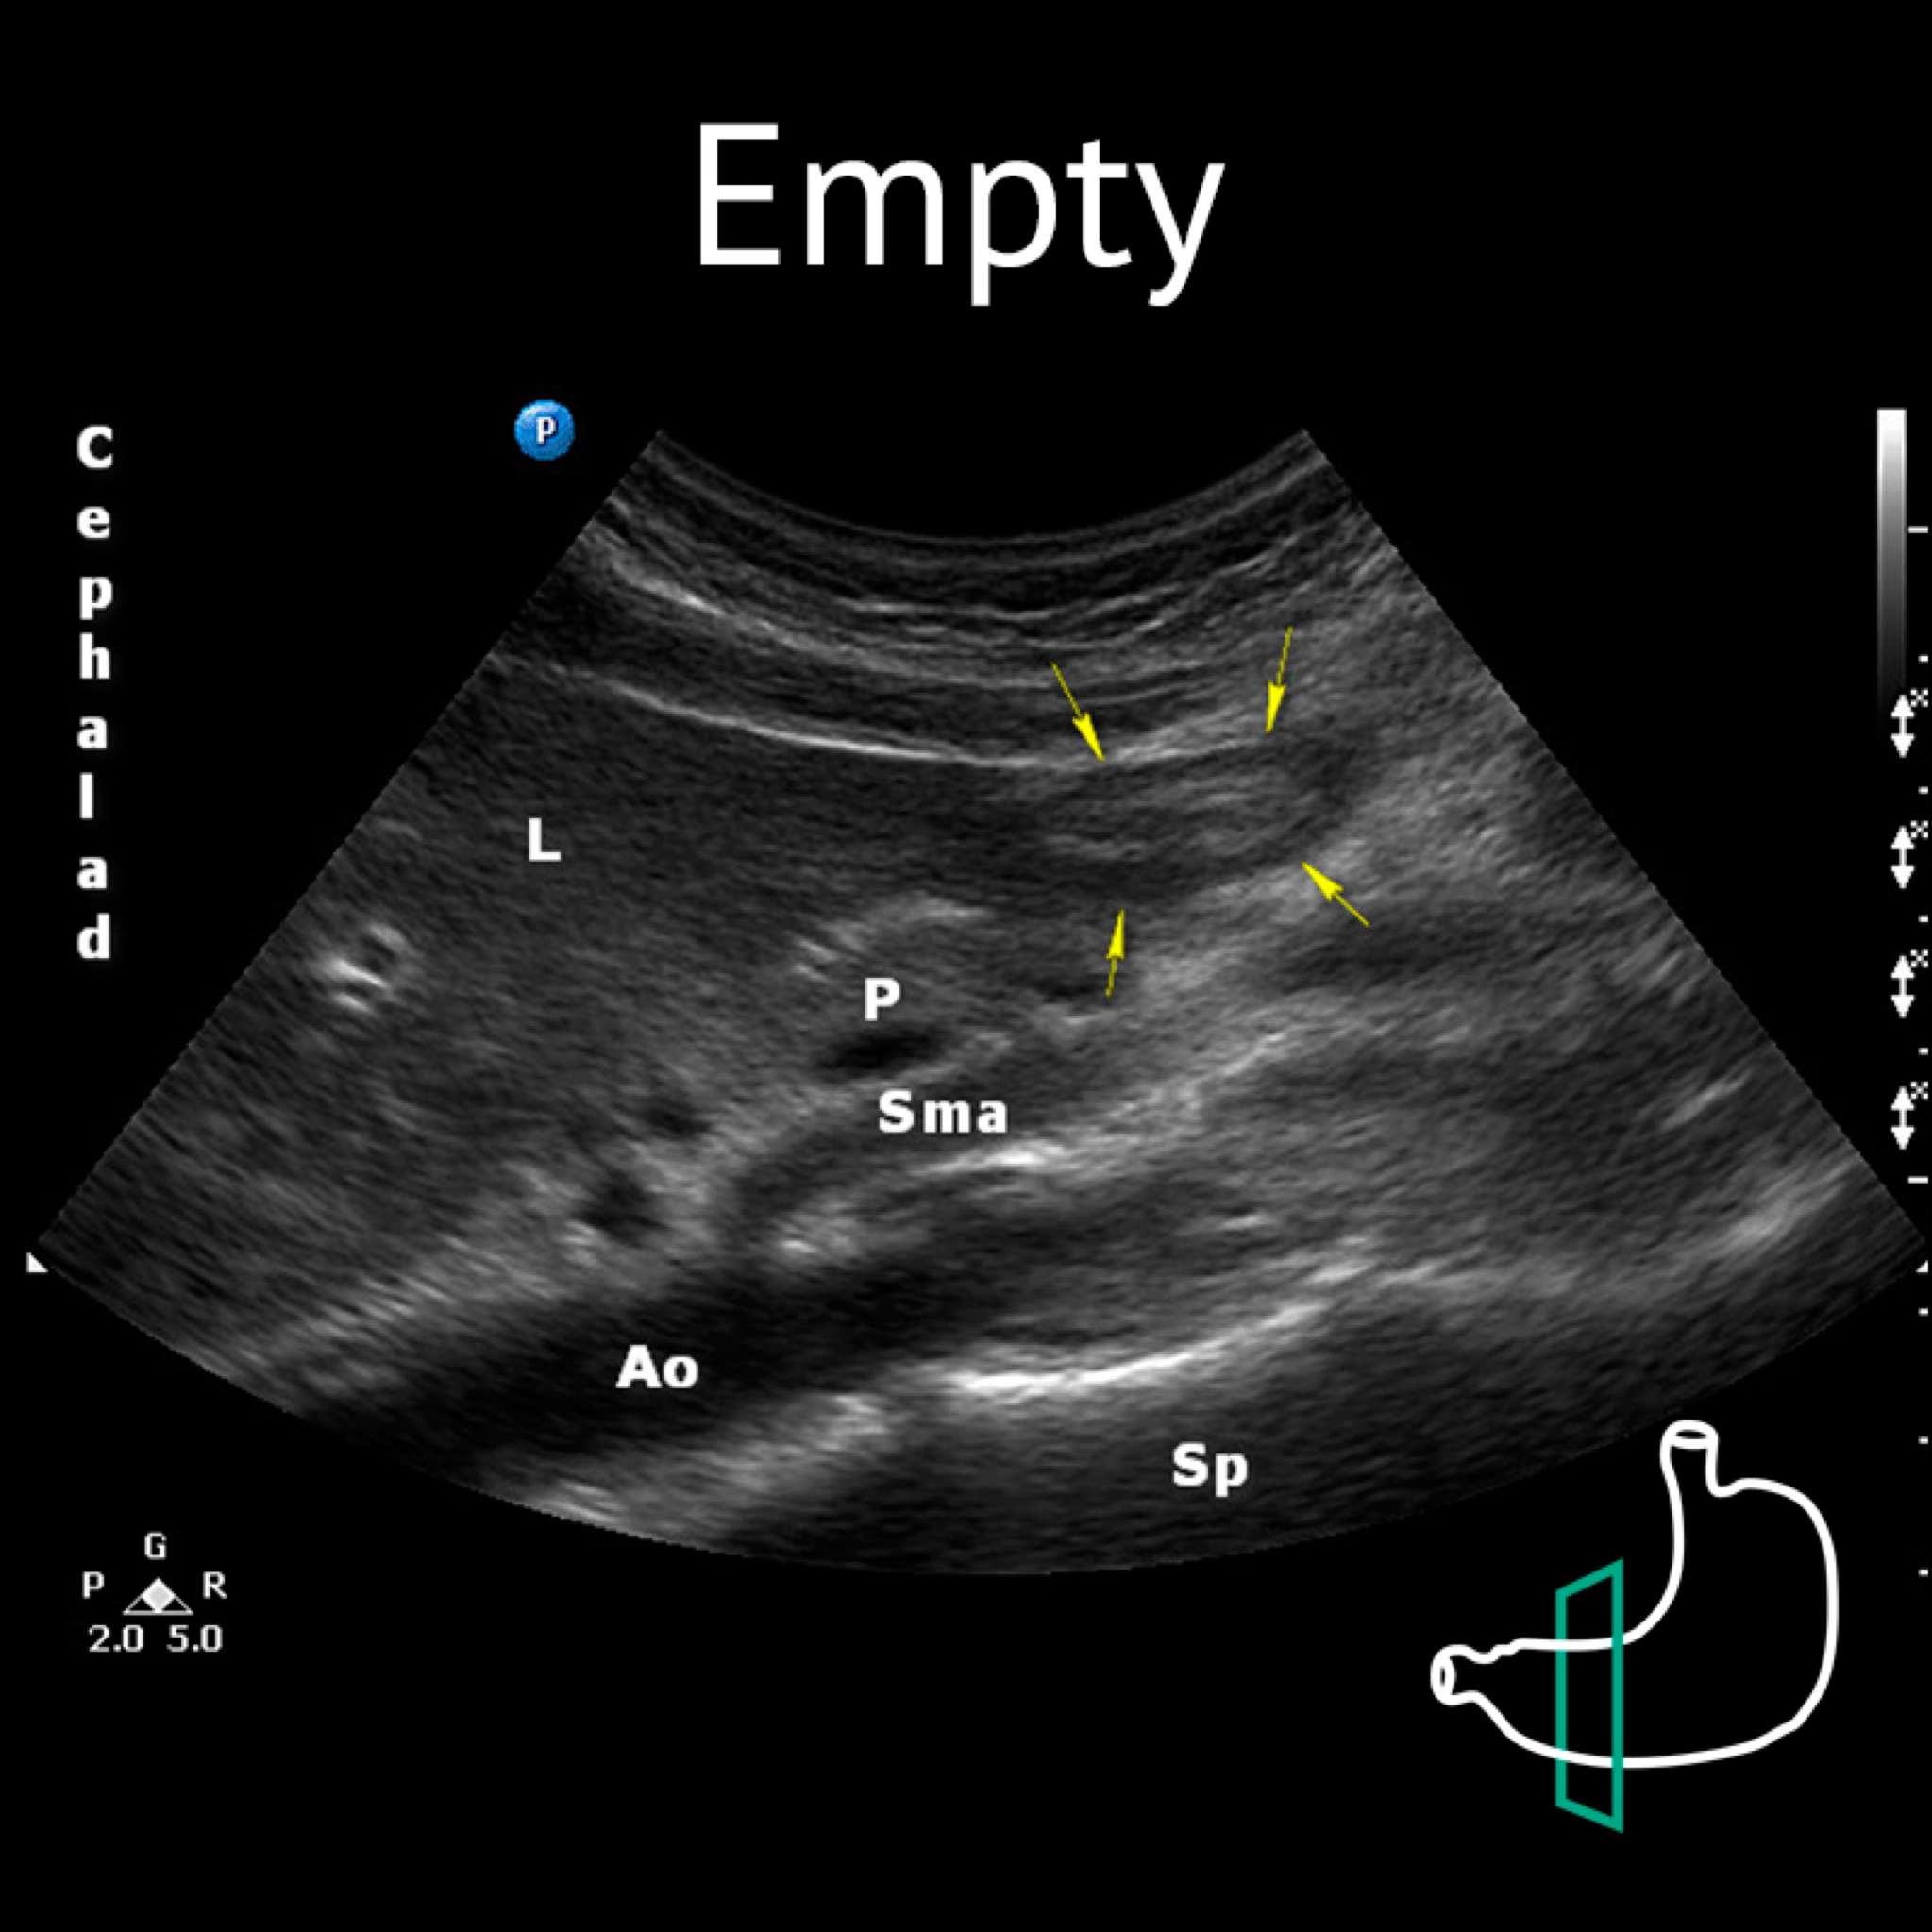

Ao: aorta; L: liver; P: pancreas; Sma: superior mesenteric artery; Sp: spine Yellow arrows: antrum

Ao: aorta; L: liver; P: pancreas; Sma: superior mesenteric artery; Sp: spine; Yellow arrows: antrum